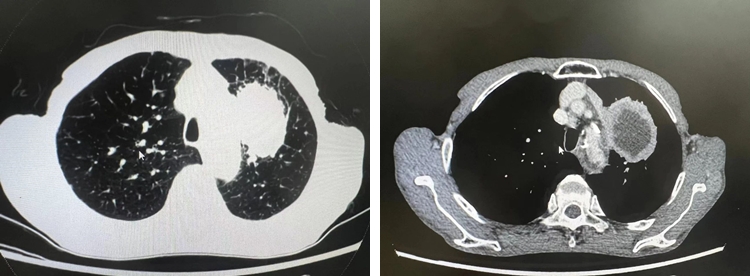

该患者在常规体检时发现左上肺存在肿物,经详细检查,肿物体积较大,约为 70mm×53mm,情况不容乐观。鉴于患者的高龄以及身体状况等多方面因素,我院迅速组织了多学科专家团队进行会诊,他们综合分析了患者各项检查指标,从手术的可行性、潜在风险以及围手术期的管理等多维度进行了全面而深入的评估。经过审慎讨论,专家们一致认为胸腔镜下肺癌根治术是目前最适合患者的治疗方案。